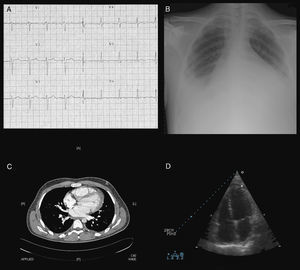

Laboratory tests revealed hemoglobin 9.3g/dl, WBC 33200/mm3 (93.8% neutrophils), platelets 512000/mm3, prothrombin activity 51.9%, AST 177U/l, ALT 108U/l, gamma-glutamyl transpeptidase 225U/l, LDH 1044U/l and troponin I 3ng/ml. C-reactive protein was 262.8mg/l, ESR 97mm/h and ferritin 37640ng/ml. Thyroid hormones, immunoglobulins and complement were normal. Rheumatoid factor, ANA, extractable nuclear antigen, anti-nDNA, antineutrophil cytoplasmic and antiphospholipid antibodies were negative. Serology, blood cultures, urine cultures and Mantoux testing was negative. A blood smear showed no abnormalities. Arterial blood gas showed partial respiratory failure. Electrocardiogram revealed sinus tachycardia with negative T in V4–6 (Fig. 1A). A chest radiography (Fig. 1B) showed global cardiomegaly and bilateral pleural effusion. Exudative pleural fluid, with smears, cultures and cytology were negative. The horaco-abdominal CT (Fig. 1C) revealed minimum pleuropericardial effusion, cardiomegaly and hepatomegaly. The echocardiogram (Fig. 1D) revealed mild-moderate pericardial effusion, an ejection fraction of 41% of the left ventricle, moderate-severe mitral regurgitation and mild to moderate mitral stenosis.

Studies that showed the presence of myopericarditis: sinus tachycardia and negative T waves in V4–V6 ECG (A), global cardiomegaly and bilateral pleural effusion on chest X-ray (B), pleuropericardial effusion and cardiomegaly on thoraco-abdominal CT (C), mild to moderate pericardial effusion on echocardiography (D).